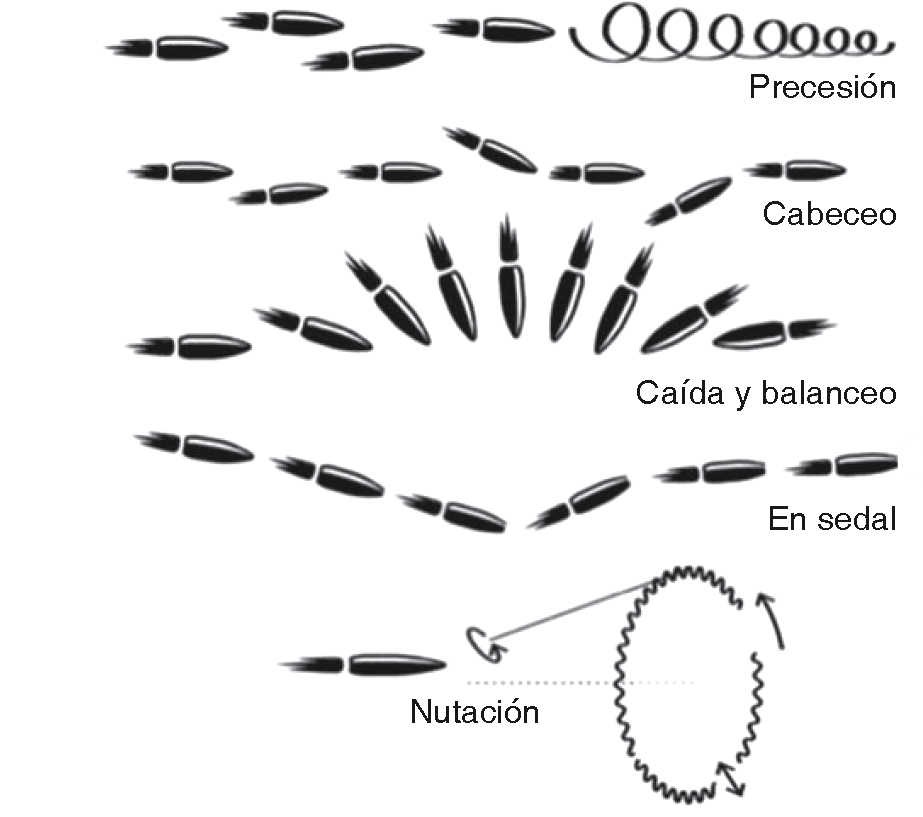

La meta es dar un soporte vital básico, estabilizar al paciente y restaurar la continuidad, función y estética facial. Para su estudio se les nombra heridas balísticas y se clasifican dentro del trauma penetrante. La física cataloga el movimiento del proyectil en tres partes, interior (dentro cañón), exterior (desde su salida hasta su impacto), terminal (penetración en objetos sólidos). Presentando estos diferentes patrones de desplazamiento: precesión, caída y balanceo, cabeceo, sedal y nutación (Figura 1).3,4 No hay un acuerdo universal para clasificarlos por velocidad: la literatura de norteamericana refiere como alta velocidad entre 610-914 m/s, el Reino Unido toma mayor a 335 m/s como alta velocidad. Sherman y Parrish los clasifican en menor a 330 m/s, media entre 330-600 m/s, y mayor a 600 m/s (Cuadro II).2,5